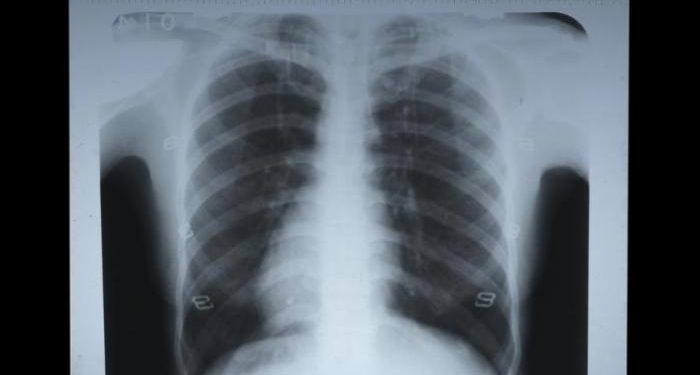

TRIBUNJATENG.COM, KUDUS – Wajah Endang sayu saat menunjukkan angka banyaknya warga Kudus yang mengidap Penyakit Paru Obstruktif Kronis (PPOK).

Penyakit yang menyerang organ vital manusia berupa paru-paru itu sepanjang Januari sampai Mei 2018 sudah mencapai 294 orang yang terserang.